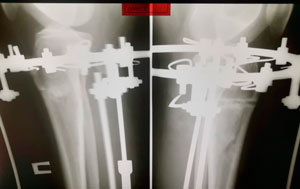

рентген в 60 дней

IMG_4850-06-08-19-08-10.JPG

IMG_4849-06-08-19-08-10.JPG